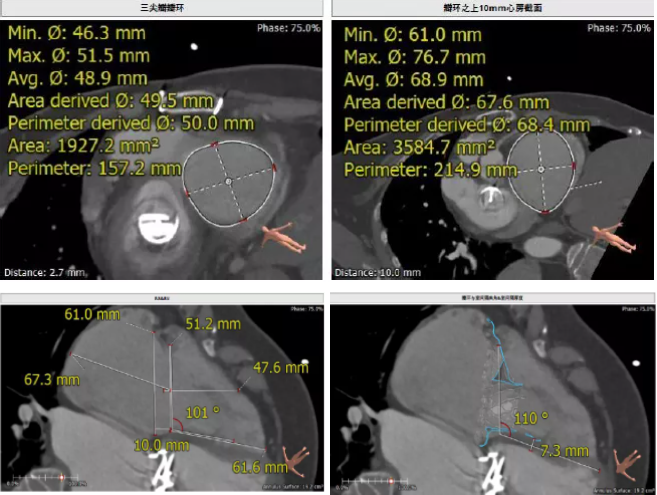

患者64歲女性,18年前接受了“正中開胸二尖瓣機械瓣置換術”,2年前超聲檢查發(fā)現(xiàn)“三尖瓣重度返流”。輾轉(zhuǎn)多地,嘗試各種治療方式,均無明顯改善。由于存在相關合并癥,傳統(tǒng)外科手術風險大,郭惠明教授團隊結合該患者CT、超聲檢查結果,對該患者的情況進行了充分的評估和討論,決定采用LuX-Valve人工三尖瓣介入瓣膜置換系統(tǒng)對患者進行微創(chuàng)介入治療,以最小的創(chuàng)傷解決患者的病痛。

術前CT評估